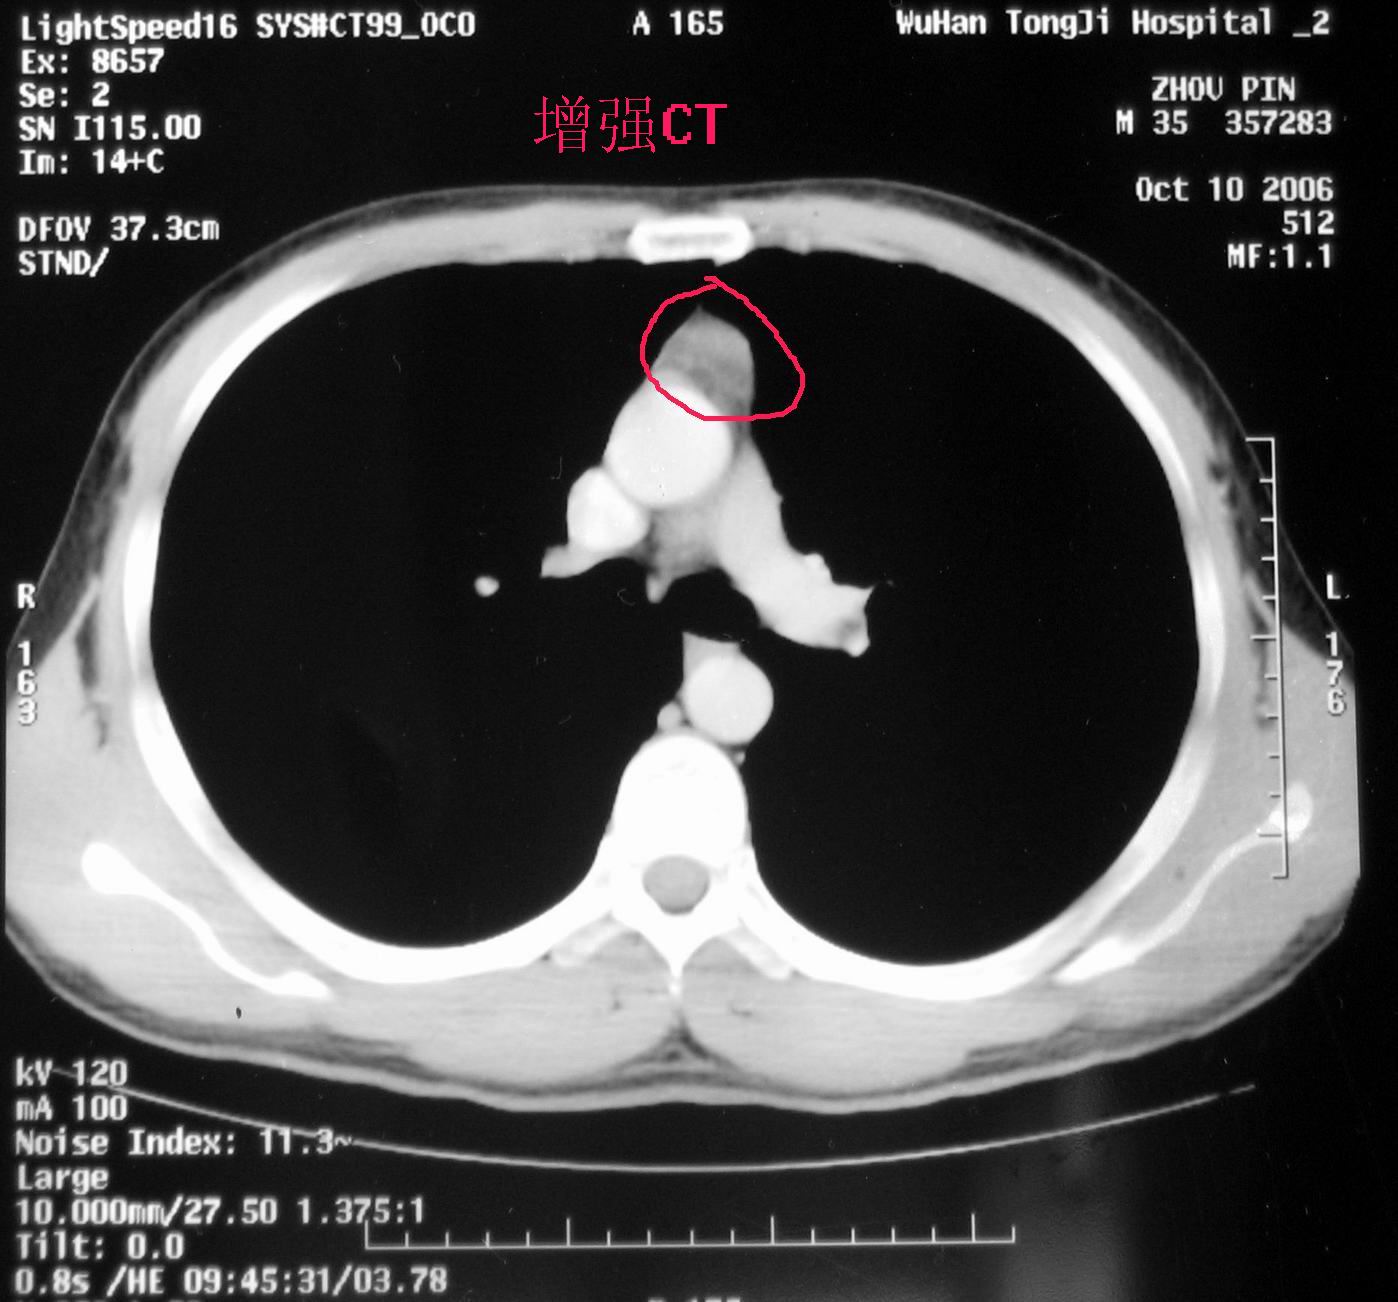

我也是迫切的希望我麻油长什么纵膈肿瘤,可是同济和肿瘤医院的影像科都说我的那个地方有直径2cm的结节,类型待查。

同济和省肿瘤医院的影像科的医生都说前纵膈上有直径2cm结节,类型待查。

1.医生所说说的那个结节存不存在?

2.如果存在,那个结节是不是残留胸腺,我这个年龄,是胸腺的可能性有多大?

3.如果不适胸腺,从ct上看,那可能是什么肿瘤?

4.这个位置的肿瘤能否穿刺活检?我在武汉市转了一圈,去了同济、协和、肿瘤、省人民医院,都说没有办法穿刺,这是真的吗?

你前纵隔内确有个结节,应该是来源于胸腺组织,不管说是未退化的胸腺、或是胸腺瘤,从目前的情况来看应该是没什么症状的良性病灶,而您的症状却非常明显,我个人感觉应该和这个没关系。可以看出您是对自己健康非常关注的人,而您的症状是如此的具体而奇怪。“我再次翻身感觉前胸骨背后有极少量液体从上而下流淌而过,估计是肿瘤与某组织的粘连被我弄破了”这是个很奇怪的主述。

同济的影像科意见是,该结节多考虑为残留胸腺,建议复查。胸外科医生在我要求下开了手术切除住院证。

协和的胸外科医生,看了ct,然后直接给我开了住院证,要我住院手术切除,说我这个年龄应该看不到这么大的胸腺。

省肿瘤医院的影像科医生意见,前纵膈占位性病变,考虑胸腺瘤的可能,前纵膈其它肿瘤待排。胸外科的医生意见,直接放疗,或手术切除。